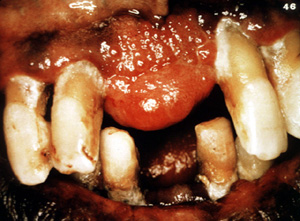

Éste es un

ejemplo bastante típico de una lesiónnodular, firme cubierta porepitelio normal. El color indica que hay proliferación vascular.

Este ejemplo

típico se ulcera focalmente pero es asintomático. Este varón de 48 años

de edad declaró que la lesión se había estado agrandando durante 5 años.

Los dientes aparecen separados. Es frecuenteque estas lesiones pueden ser bastante agresivas y pueden cambiar

de sitio a los dientes.

Esta gran

lesión se extendió bien en lingual y cambió de sitio algunos de los

dientes. Los granulomas periféricos lograrán un tamaño considerable

sin tratamiento. La terapia es la biopsia por escisión . Puede ser

necesario extender la cirugíaal

hueso subyacente para eliminar la lesión. También se indica la

eliminación de estímulos irritantes.